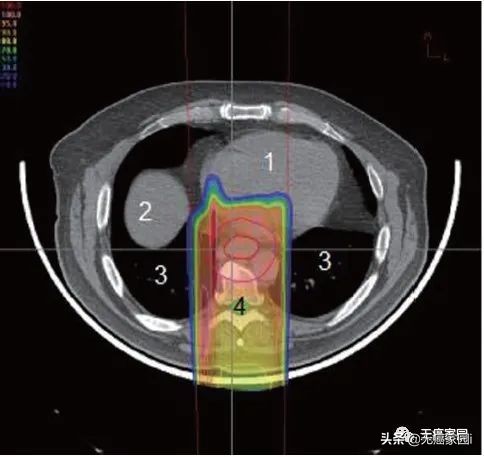

食道位于后纵隔内,靠近几个关键结构,即肺、脊髓和心脏。最大限度地减少对这些关键结构的毒性降低了患者的整体治疗发病率和死亡率。然而,必须在放射野中考虑足够大的边缘以覆盖肿瘤区域和受累淋巴结,这使周围器官面临更大的风险。肺剂量是食管癌放射期间毒性的主要危险因素。为了将脊髓剂量保持在容许范围内,通常需要使用多个倾斜角度的光束(图1~3)。这就导致肺部接收到大量辐射剂量,从而产生放射性肺炎和术后肺部并发症。

图3:单条后质子束治疗食管的轴位图;1. 心;2. 肝脏;3. 肺;4. 脊髓